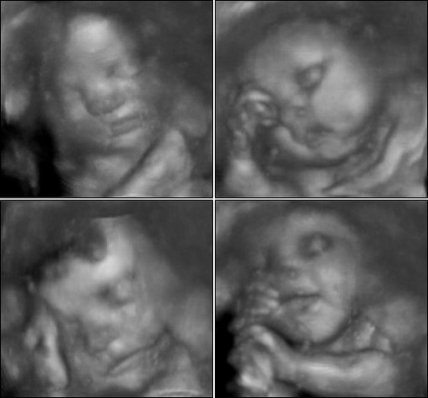

32 неделя беременности как выглядит ребенок фото

32 НЕДЕЛЯ БЕРЕМЕННОСТИ УЗИ, ВЕС И РАЗМЕРІ ПЛОДА: КАК ВЫГЛЯДИТ РЕБЕНОК

На 32 неделе беременности размер Вашего ребенка достиг 38-42 см, вес плода на 32 неделе беременности составляет 1600-1800 г.

Ребенок набирает вес. Жировой слой, обеспечивающий теплообмен, согревает малыша. Сейчас необходимость в пушковых волосах (лануго), которые покрывали и тельце крохи и согревали его, отпала. Поэтому они постепенно выпадают. Окончательно распрощаться с лануго малыш сможет за несколько дней до родов или через неделю после них. А вот на головке крохи начинают появляться настоящие волосы.

Пропорции головы и тела напоминают новорожденного ребенка. Морщинки, которые покрывали личико малыша, разглаживаются, кожа на теле светлеет, перестает быть красной и сморщенной.